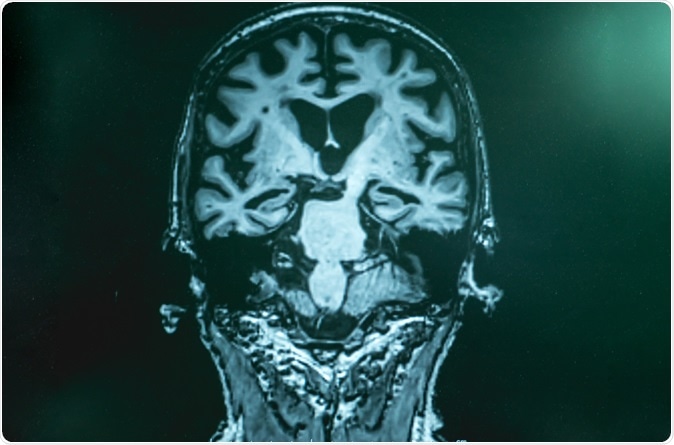

Alzheimer

Alzheimer's disease with MRI. Image Credit: Atthapon Raksthaput / Shutterstock